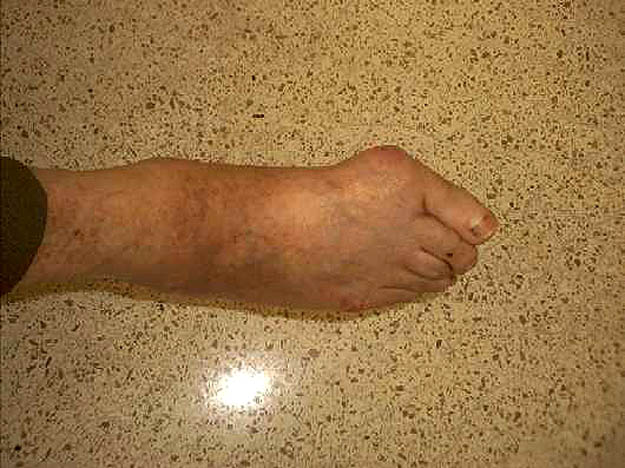

Malformación congénita de pie izquierdo.